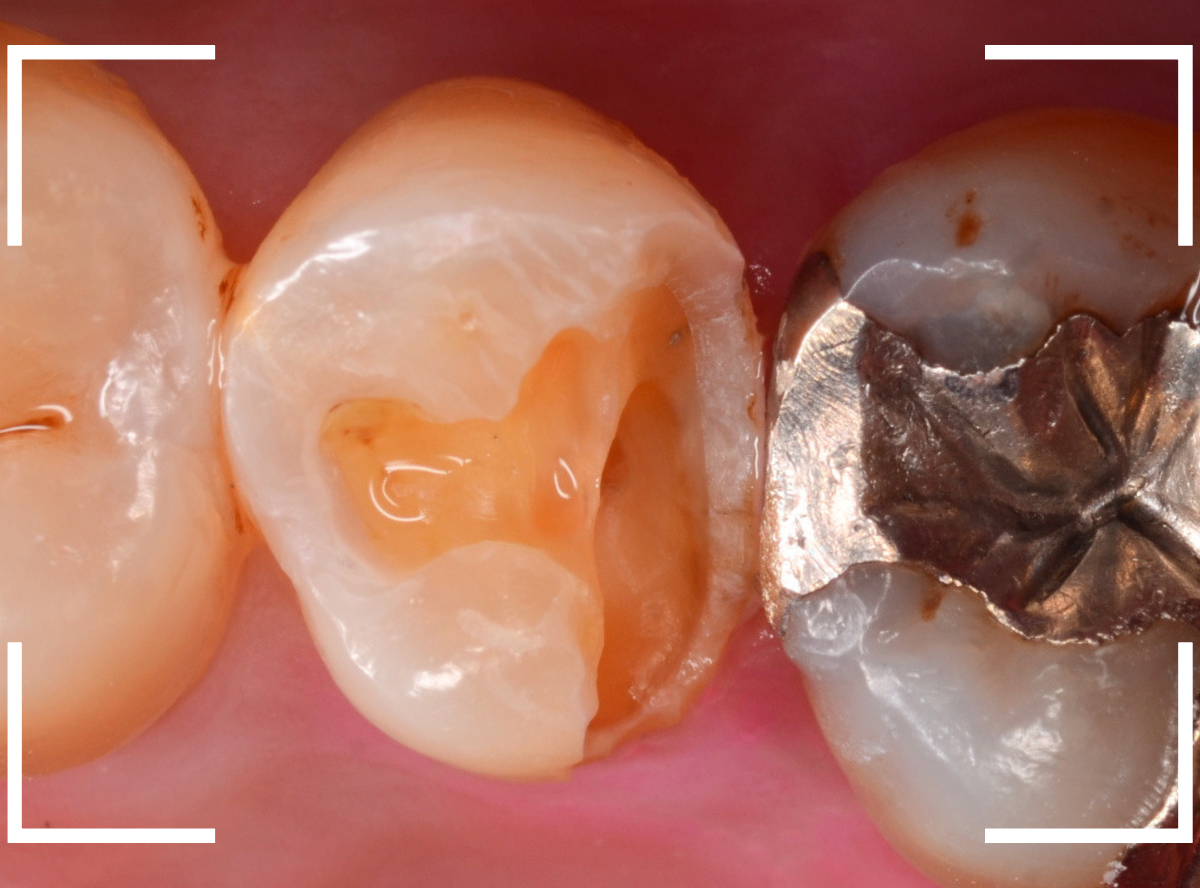

虫歯を全て除去しました。

幸い、あまり多く削る事なく進められたので良かったです。

手前の歯のつめ物も外します。

こちらもお薬が入っていますが、外して中を調べます。

こちらは中も問題なかったです。

奥歯は歯に優しいファイバー・コアで再製し、型取りします。